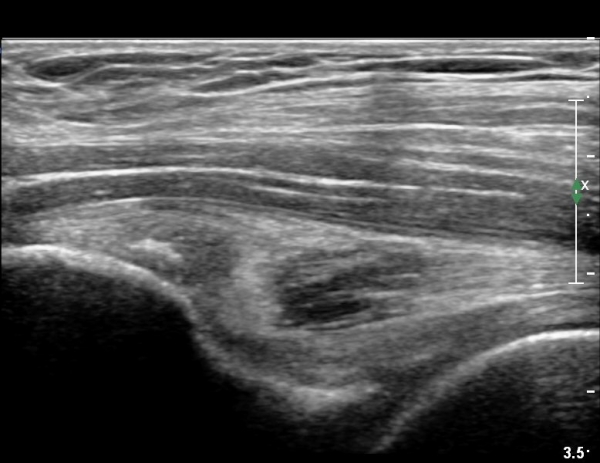

ÃÊÀ½ÆÄ °Ë»ç